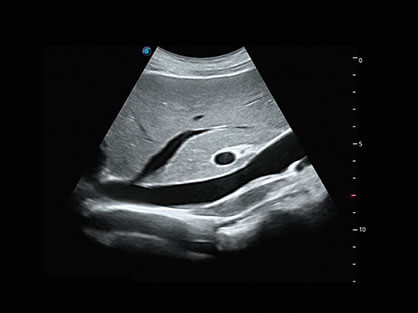

临床图